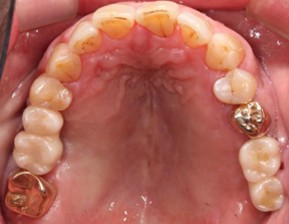

70代 女性

治療前

治療後- リスク・副作用

- 術後疼痛、歯肉腫脹

- 治療の費用

- 合計¥1,126,000(税込)

【内訳】

インプラント(2本)¥880,000

その他費用¥246,000

(薬・注射・レントゲン・ソケットリフト骨造成・サージカルステント・CT・データ分析) - 年齢/性別

- 70代/女性

- 患者の具体的な症状

- 右上56欠損のため義歯を使用していたが不安定で十分噛めないため、インプラント治療を希望

- 検査方法

- コーンビームCT、レントゲン撮影

- 診断結果

- 右上56欠損

- 治療詳細

- 右上56部、コーンビームCTによる画像診断で垂直的な骨高、骨密度の不足のため、ソケットリフトによる骨再生治療とインプラント埋入2本を同時にショートインプラントを用いて行った。

- 通院回数

- 7回

- 治療期間

- 7か月